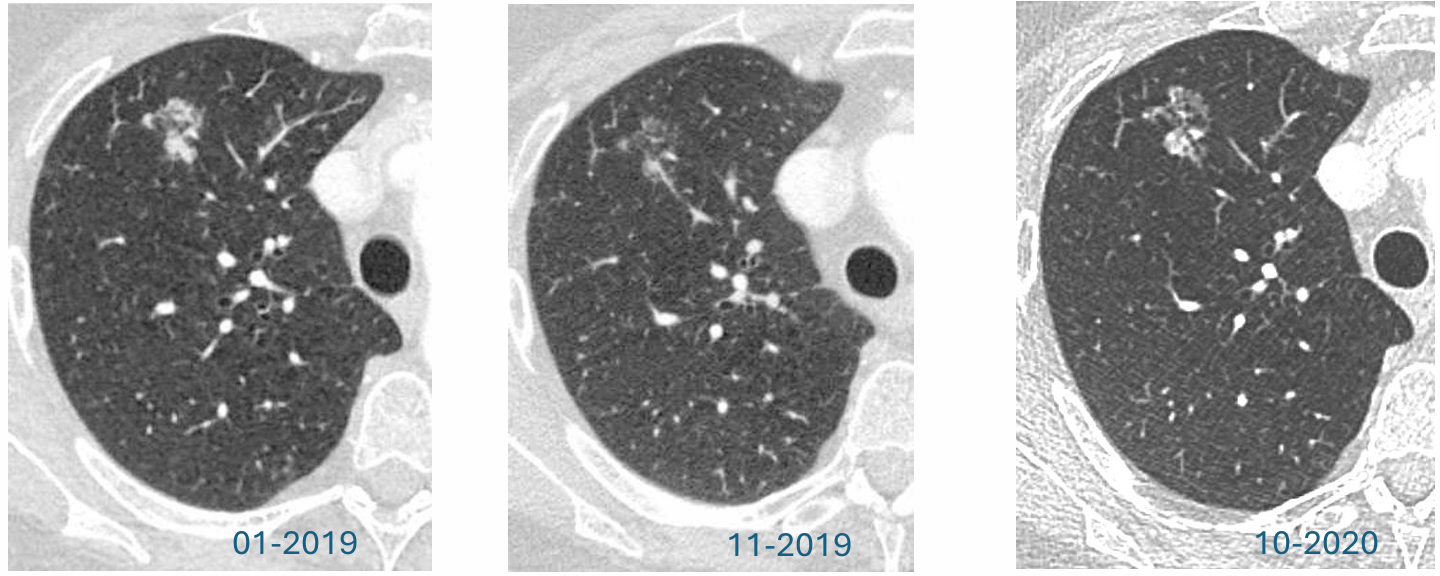

中期随访:误导性的病灶缩小

2019年11月,CT随访:距离初次发现约10个月后,CT复查显示令人意外的结果:结节明显缩小。影像表现:原有的亚实性(磨玻璃)成分变得“几乎难以辨认”。更重要的是,原先大于8mm的实性成分已缩小至仅3mm。这种显著的消退强烈指向炎性或感染性病变,在临床实践中,这通常被视为良性过程的有力证据,大多数情况下可能导致停止进一步的肿瘤相关随访。

尽管病灶明显缩小,但经验丰富的影像科医生注意到关键细节:病灶并未完全消失。此时,临床面临两难的鉴别诊断:炎症可能性大,但影像科医生的推理是,感染性病变通常会完全消散。腺癌可能性小,但影像科医生的顾虑是,纤维化病灶应保持稳定(而非缩小),而部分腺癌可能表现出多变的形态。病灶的“未完全消失”是核心疑点。在一次学术讨论中,针对此情况提出包括“停止随访”、“12个月后随访”和“再次活检”在内的多种管理选项,反映临床决策的高度不确定性。最终,影像科医生基于“病灶未完全吸收”的理由,坚持要求进行为期1年的再次CT随访,以明确病灶的最终转归。

长期随访:病情逆转

2020年10月,CT随访:距离上次“缩小”的CT检查11个月后,复查CT显示,病灶出现戏剧性的逆转。影像表现:原先缩小的亚实性结节出现显著增大。关键变化:其内部的实性成分在11个月内,从3mm快速增长至11mm。这种实性成分的明确增长是恶性肿瘤的明确信号,至此已基本排除良性炎性病变的可能性。